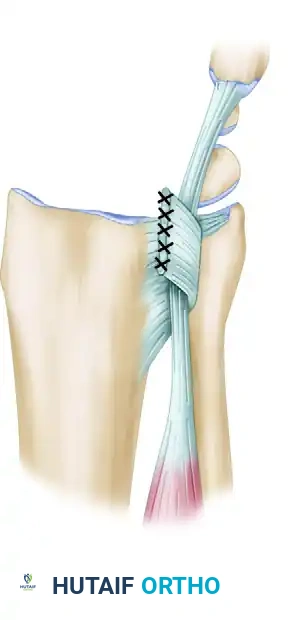

Figure 1: Stabilization of the extensor carpi ulnaris with a retinacular sling. The flap is based on the fibrous wall between compartments four and five, preventing volar subluxation of the tendon during forearm rotation.